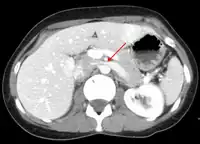

- Compression of the left renal vein (marked by the arrow) between the superior mesenteric artery (above) and the aorta (below) due to nutcracker syndrome